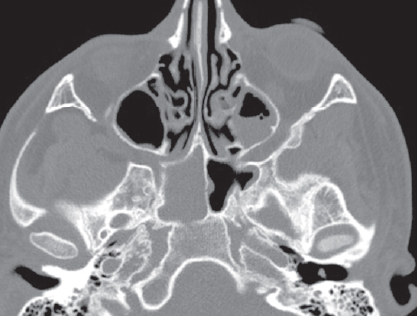

04.06.2021 выполнена мультиспиральная компьютерная томография (МСКТ) ОНП (рис. 1): определяется субтотальное снижение пневматизации левой половины лобной пазухи, задняя ее стенка сохранена, нельзя исключить щелевидные истончения. Затенение лобно-носового кармана слева, клетки решетчатого лабиринта слева частично затенены, деструкции в области переднего основания черепа убедительно не прослеживается. Отмечается пристеночное снижение пневматизации с уровнем жидкости в левой верхнечелюстной пазухе. Округлое новообразование в правой верхнечелюстной пазухе — киста. Пневматизация пазухи клиновидной кости, клеток сосцевидных отростков и барабанных полостей не нарушена.

Рис. 1. Мультиспиральная компьютерная томография околоносовых пазух и головного мозга от 04.06.2021: коронарная (а) и аксиальная (b) проекции в режиме skull, субтотальное затенение левой лобной пазухи, костная деструкция отсутствует; аксиальная (c) и сагиттальная (d) проекции в режиме brain, эпидуральная эмпиема левой лобной области головного мозга; коронарная (е) и аксиальная (f) проекции в режиме brain с контрастным усилением. Эпидуральная эмпиема левой лобной области головного мозга. Отчетливо прослеживается капсула

Fig. 1. Multispiral computed tomography of the paranasal sinuses and brain from 04.06.2021: coronal (а) and axial (b) projections in the protocol of the skull, subtotal shading of the left frontal sinus, no bone destruction; axial (c) and sagittal (d) projections in the brain mode, epidural empyema of the left frontal area of the brain; coronary (е) and axial (f) projections in brain mode with contrast enhancement. Epidural empyema of the left frontal region of the brain. The capsule is clearly visible

04.06.2021 выполнено МСКТ головного мозга: определяется наличие очага гнойного воспаления, исходящего из левой лобной пазухи и отграниченного от вещества мозга капсулой. Наличие двух очагов малого размера («отсевы»), менее 1 см, с признаками формирующейся капсулы. Отмечается зона отека мозгового вещества между очагами.